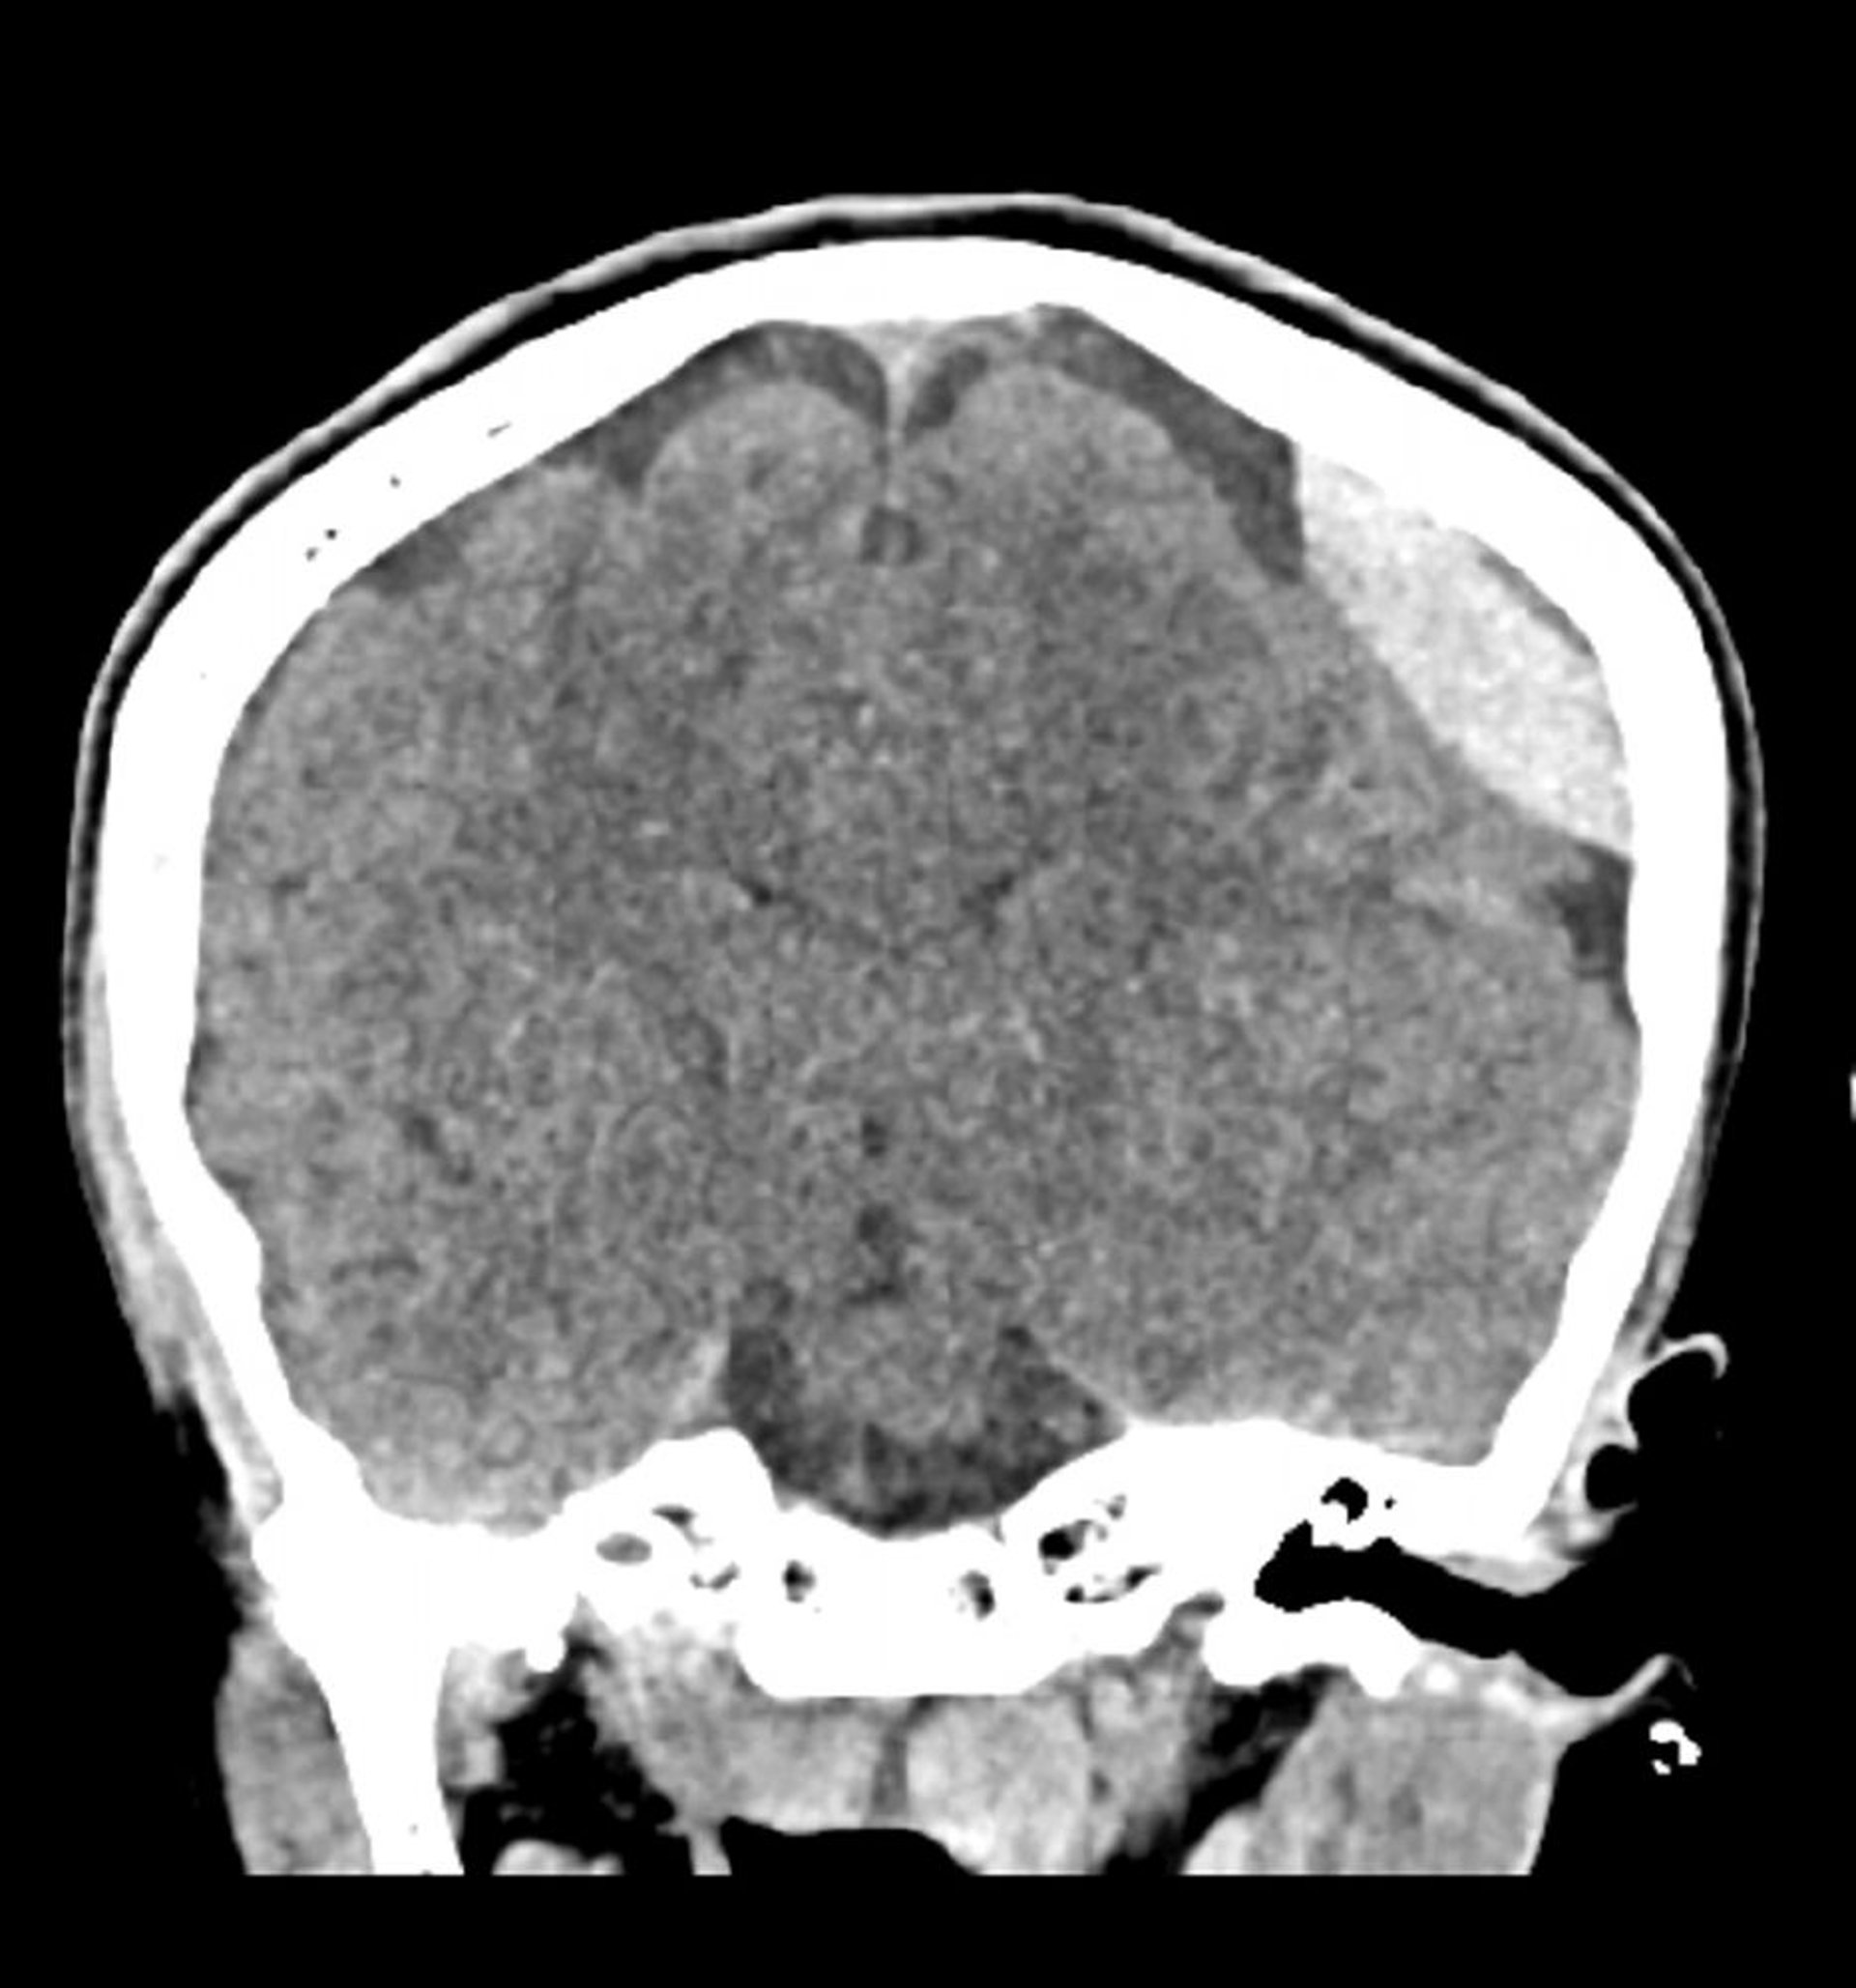

Hémorragie épidurale (TDM coronale)

Hyperdensité classique en forme de lentille qui ne s'étend pas à travers les lignes de suture.